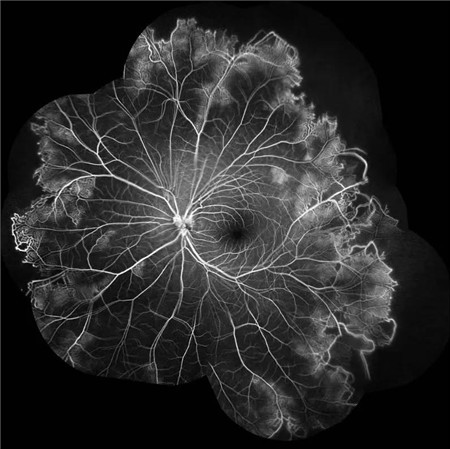

特发性视网膜血管炎、动脉瘤和视神经视网膜炎综合征(Idiopathic Retinal Vasculitis, Aneurysm, and Neuroretinitis syndrome,简称IRVAN综合征)是一种病因不明的较为少见的视网膜血管炎性疾病,此病症常在30-40岁发病且多为女性发病。在发病的前期,如果进行及时有效的治疗干预,预后效果多数较好。但一拖再拖,错过最好的治疗时间,可引起严重的并发症。在这里提醒大家,一定要密切关注自己眼部突发情况的出现,警惕眼前突然发生黑影飘动,视力下降的情况,尽早就医。

经过详细的眼底检查后,患者被诊断为IRVAN综合征引起的右眼黄斑裂孔,张风院长带领医生团队为患者施局右眼玻璃体切除+剥膜+眼内光凝+气液交换手术,经过半个月的恢复,患者右眼术后视力由术前0.3-达到0.6-的状态,且裂孔呈逐渐闭合状态。

视盘附近的动脉和动脉分叉处出现瘤样动脉扩张,视盘充血,边界不清,引起视盘周围视网膜内硬性渗出;视盘周可有少量放射状出血。

静脉不规则扩张和血管鞘膜,周边部小血管广泛闭塞,交界处毛细血管扩张和异常吻合。

严重者可发生从周边到黄斑的血管闭塞和缺血、玻血、新生血管性青光眼,最终视神经萎缩。